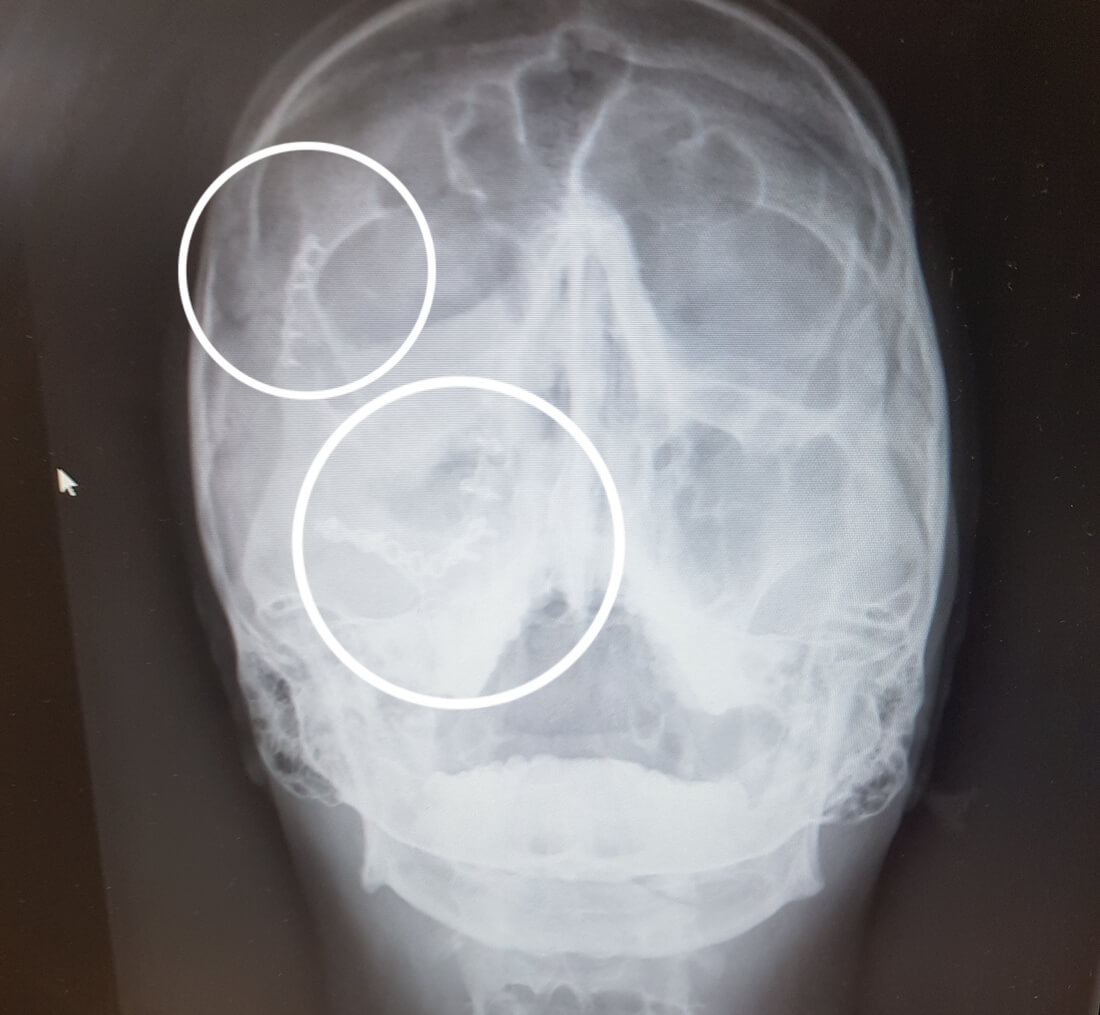

RTG s vyznačením titanu.